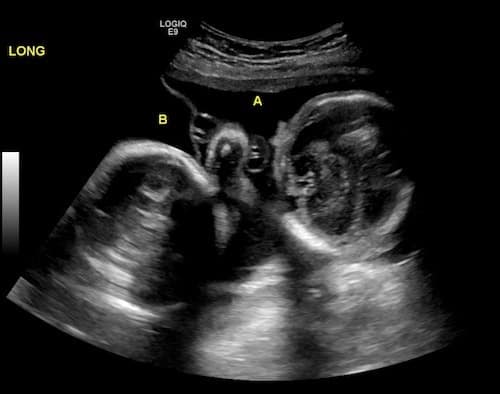

Ultrasound Photos at 25 Weeks Pregnant With Twins